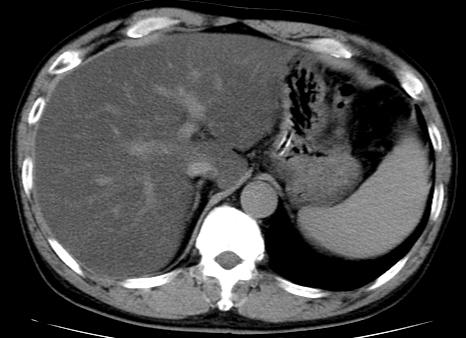

3.下图中肝硬化的CT表现描述错误的是:

A、肝内大小不等结节

B、肝脏表现凹凸不平

C、脾大

D、肝硬化增生结节增强后明显强化

选项:

A: 肝硬化再生结节大多增强动脉期无强化,强化形式和肝脏同步

B: 肝硬化再生结节大多增强动脉期无强化,强化形式和肝脏同步

C: 肝硬化再生结节大多增强动脉期无强化,强化形式和肝脏同步

D: 肝硬化再生结节大多增强动脉期无强化,强化形式和肝脏同步

答案: 【 肝硬化再生结节大多增强动脉期无强化,强化形式和肝脏同步】